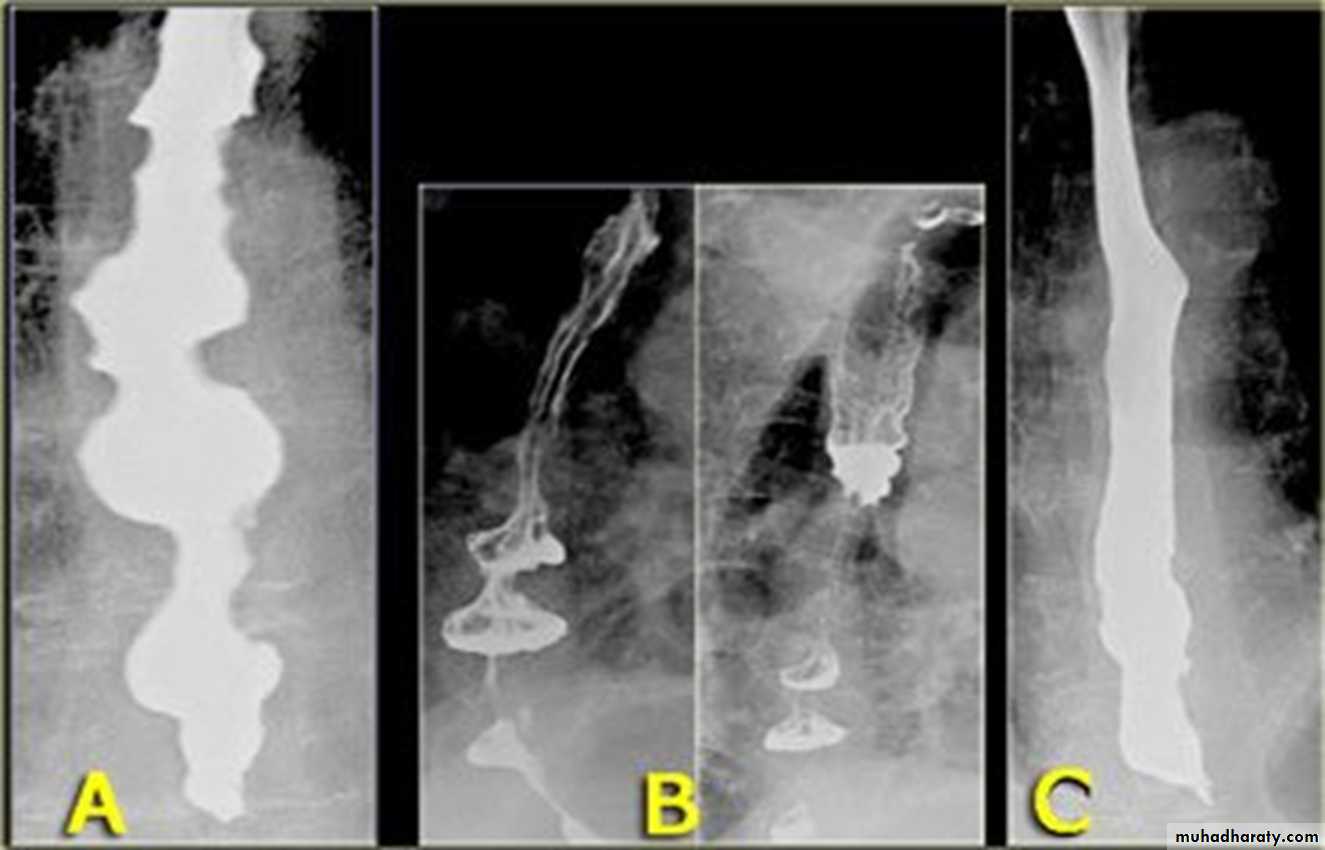

Tertiary contractionsDiffuse esophageal spasm

Nutcracker eosaphagus (crock screw)

tertiary contractions

Diffuse esophageal spasm

Diffuse esophageal spasm produces intermittent contractions of the mid and distal esophageal smooth muscle, associated with chest symptomsCongenital Anomalies

Annular Carcinoma

Narrowing :

1-Constant.

2-Irrigular .

3-Variable length.

4- Shouldering sign.

5-Fistula (double tract).

6-Soft tissue shadow of the mass

1-Constant narrowing.

2- Long length (lower third).

3-Smooth and regular.

4-Mild proximal dilatation.

5-No shouldering sign.

6-Smooth tapering

( funnel shape).